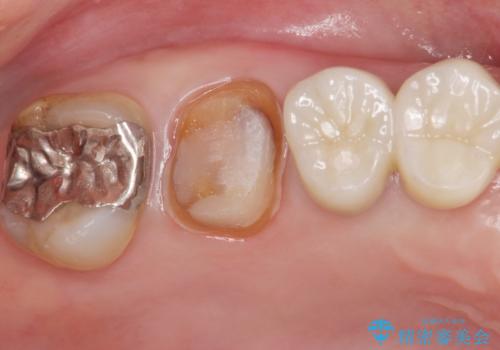

- メタルの詰め物がされている歯が欠けてしまった患者様です。

メタルを外すと中で虫歯が広がっていました。

拡大鏡下で虫歯を取り切った後、フルジルコニアクラウンにて治療しました。